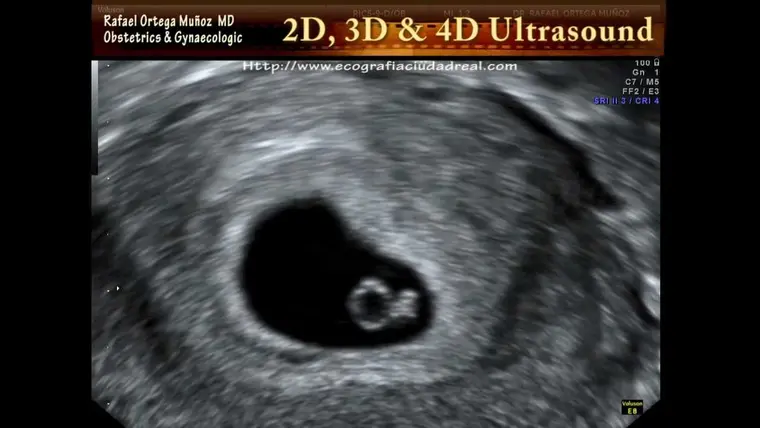

O marco mais emocionante desta semana é o início da formação do coração. O sistema circulatório, juntamente com o coração, é o primeiro sistema a entrar em funcionamento no desenvolvimento embrionário. Seu bebê já possui dois pequenos tubos cardíacos que começam a se unir para formar um coração primitivo, do tamanho de uma semente de papoula. Mesmo ainda sendo rudimentar, este pequeno coração já está batendo com um ritmo próprio!

Você sabia? O coração do seu bebê nesta semana já bate aproximadamente 100 vezes por minuto, quase o dobro do seu próprio ritmo cardíaco! Este pequeno coração já pode ser detectado em ultrassons transvaginais especializados.